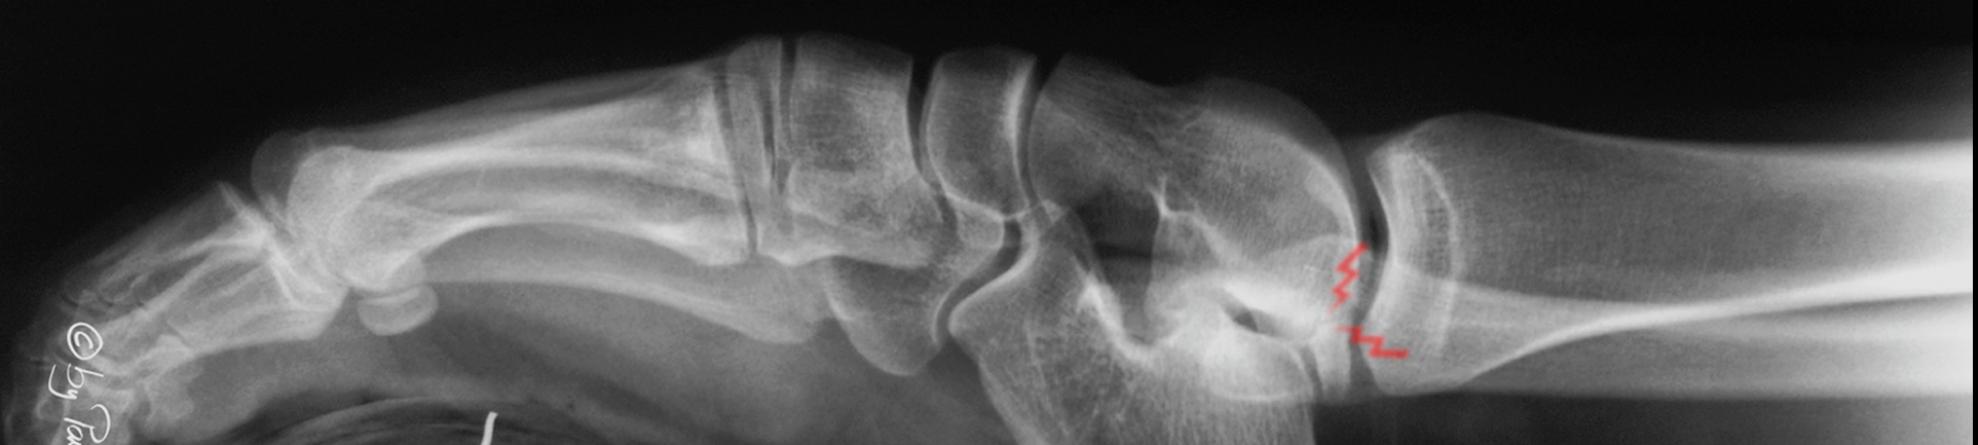

Hallux rigidus

34-year-old healthy very active female.